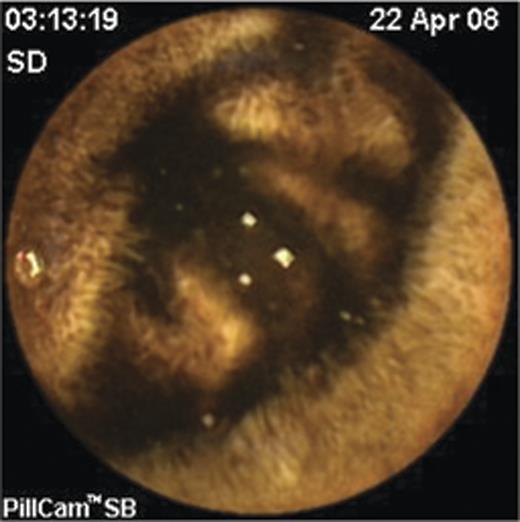

The laboratory tests showed a hemoglobin level of 6.5 mg/dl, urea 130 mg/dl and creatinine of 3.5 mg/dl. The patient was treated conservatively. An isotopic study with Tc-99 did not reveal any bleeding source. Computed tomography was initially interpreted as normal. A VCE study was performed that identified a submucosal bulge with a central ulceration in the proximal third of the small bowel (Fig. 1). More distally in the small intestine melena could be seen by the capsule (Fig. 2). Revision of the CT scan confirmed the VCE finding and showed a lesion of fat density in jejunum.

Videocapsule endoscopy image of a submucosal bulge with a superficial ulceration (arrow) in the proximal small intestine.

In our patient, the bleeding source was correctly diagnosed by the VCE. The unique VCE image (Fig. 1) of the jejunal lipoma with a superficial ulceration correlated surprisingly well with the finding that was eventually seen within the resected surgical specimen (Fig. 3). This case also supports the use of VCE as the initial modality for investigation of obscure gastrointestinal bleeding even in the hospital setup after ambulatory investigation failed due to problems of compliance.